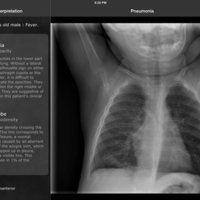

RealWorld Radiology is your ultimate guide to the basics of thoracic imaging. Learn to read chest X-rays in no time and discover the most frequent diagnoses through multiple fully annotated examples.

- Clinical information regarding the patient and mode of presentation

- Detailed radiologic interpretation

Our cases have been especially selected for their high pedagogical value and real-world representativeness. They can be classified either by diagnosis (e.g. pneumonia, atelectasis, pulmonary fibrosis) or by actual radiological finding (e.g. alveolar opacities, interstitial opacities, silhouette sign), making the learning of the differential diagnosis easier than ever while keeping each case easy to find for quick access.

Test your knowledge with the Quiz mode and check if what you see matches the radiologist's findings.